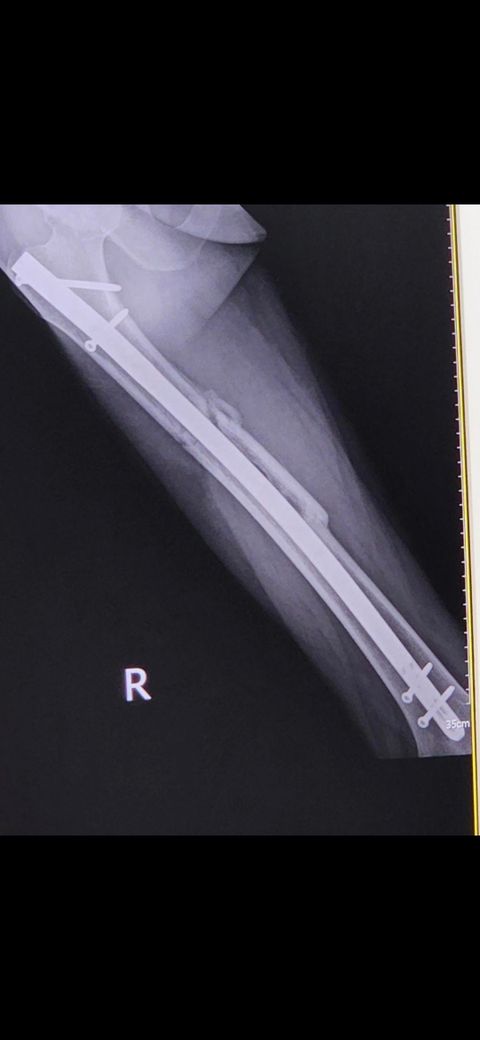

비급여 양쪽다리 철심 제거수술 비용 및 기간이 어떻게 될까요?

보험이 적용이 안되는 상황이고 오른쪽 다리엔 허벅지 뼈쪽에 길게 철심이 박혀있구요왼쪽 무릎은 철심 두개? 박혀있어요 양쪽 다리 한번에 뺄 수 있나요? 보험을 받지 못하는 상황이라 비급여 가격이 어떻게 되는지 궁금합니다 MRI 찍은게 있긴한데 1년 넘었습니다 그거 가져가도 되나요? 회복기간은 어떻게 될까요?

오른쪽다리

• 1번 째 사진